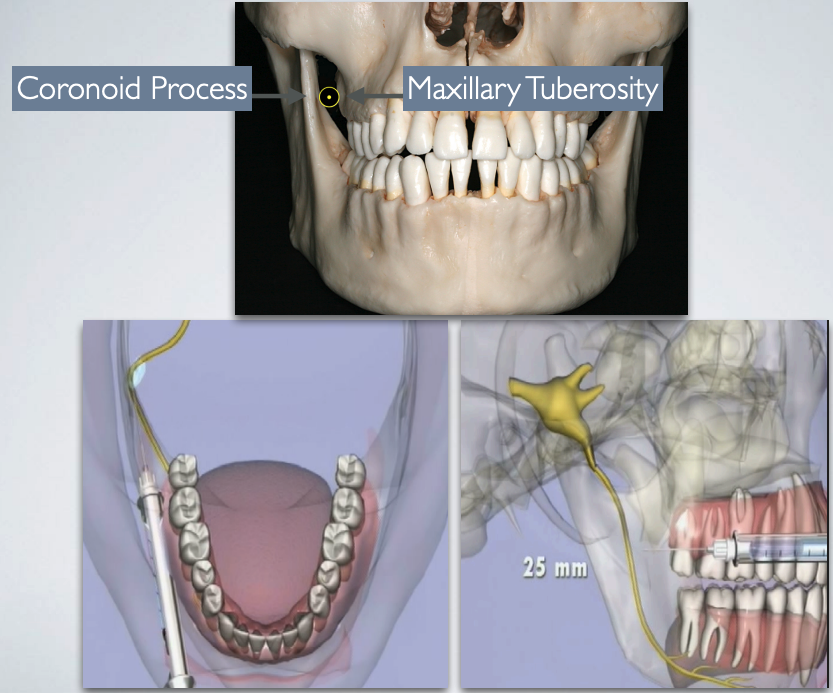

target area of which technique?

gow gates technique

what is the target point for GOW-GATES MANDIBULAR NERVE BLOCK?

Lateral aspect of condylar neck

Use both intra-oral and extra-oral landmarks to establish the path of insertion

what extra oral landmarks are used for GOW-GATES MANDIBULAR NERVE BLOCK?

what intra oral landmarks are used for GOW-GATES MANDIBULAR NERVE BLOCK?

barrel of syringe in corner of mouth on opposite side

height of insertion = maxillary occlusal plane

needle tip just below ML cusp of maxillary 2nd molar + just distal to maxillary 2nd molar

what is the average depth of needle insertion with GOW-GATES MANDIBULAR NERVE BLOCK?

25 mm